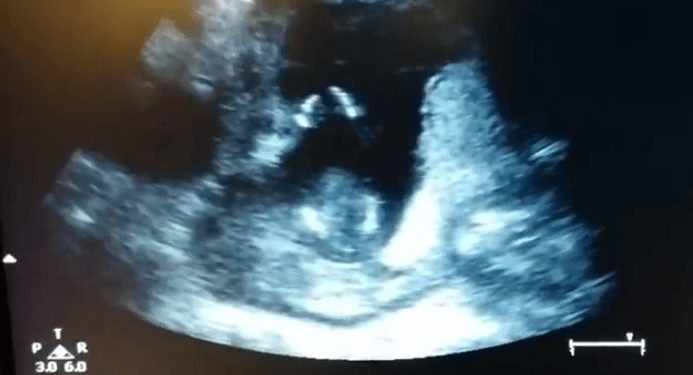

È diventato, in pochi giorni, uno dei video virali più cliccati nel Web, un feto nel grembo della mamma batte le mani a ritmo di musica durante un’ecografia di controllo. Ormai le tecniche di indagine diagnostica medica mostrano, nei minimi dettagli, le evoluzioni del feto durante la sua crescita, abbiamo visto, tra l’altro, attraverso un’ecografia 4D, come reagiscono i feti al fumo nell’utero ma questo video ha davvero dell’incredibile.

Jen Cardinal è una donna che, in compagnia del marito, giunta alla sua 14esima settimana di gravidanza, si reca dal ginecologo per un controllo di routine e durante l’ecografia vive un’esperienza davvero unica e indimenticabile.

Mentre il ginecologo effettua l’ecografia si vede che il bimbo batte le mani e alla mamma viene la brillante idea di intonare “Se sei felice e tu lo sai batti le mani” mentre il papà riprendeva il tutto. Nel video, diventato immediatamente virale, si percepisce la gioia di mamma e papà. Poco importa se il video sia stato o meno ritoccato poiché quello che importa è l’emozione trasmessa a tutti coloro che lo hanno guardato.

Secondo il ginecologo, blogger e scrittore Gunter Jen, intervistato da BuzzFeed proprio a proposito di questo video, a 14 settimane di gestazione il feto non è in grado di effettuare movimenti di proposito e soprattutto a ritmo di musica e dichiara: «Le mani si colpiscono a vicenda, ma noi non consideriamo ciò un applauso. Quello che si vede è solo movimento fetale, un gesto inconsulto che con un po’ di fantasia e un programma di editing adeguato può sembrare tale. È un po’ come guardare le nuvole e vedere determinate forme».